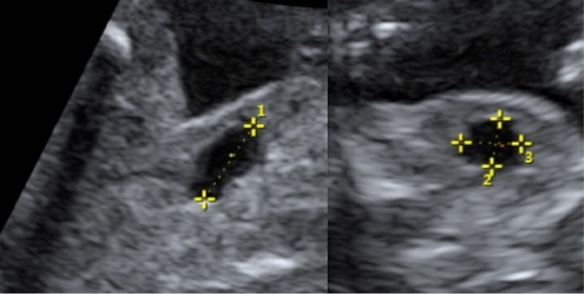

Repeatability of volume calculations of the fetal urinary bladder

Trude Sætherhaug, Marit Hølmo Fasting, Maria Aurora H. Røset, Mike Naylor, Harm-Gerd K. Blaas, Torbjørn M. Eggebø

Abstract 78 | HTML Downloads 36 PDF Downloads 37 | DOI https://doi.org/10.14440/bladder.2016.75

Page e24